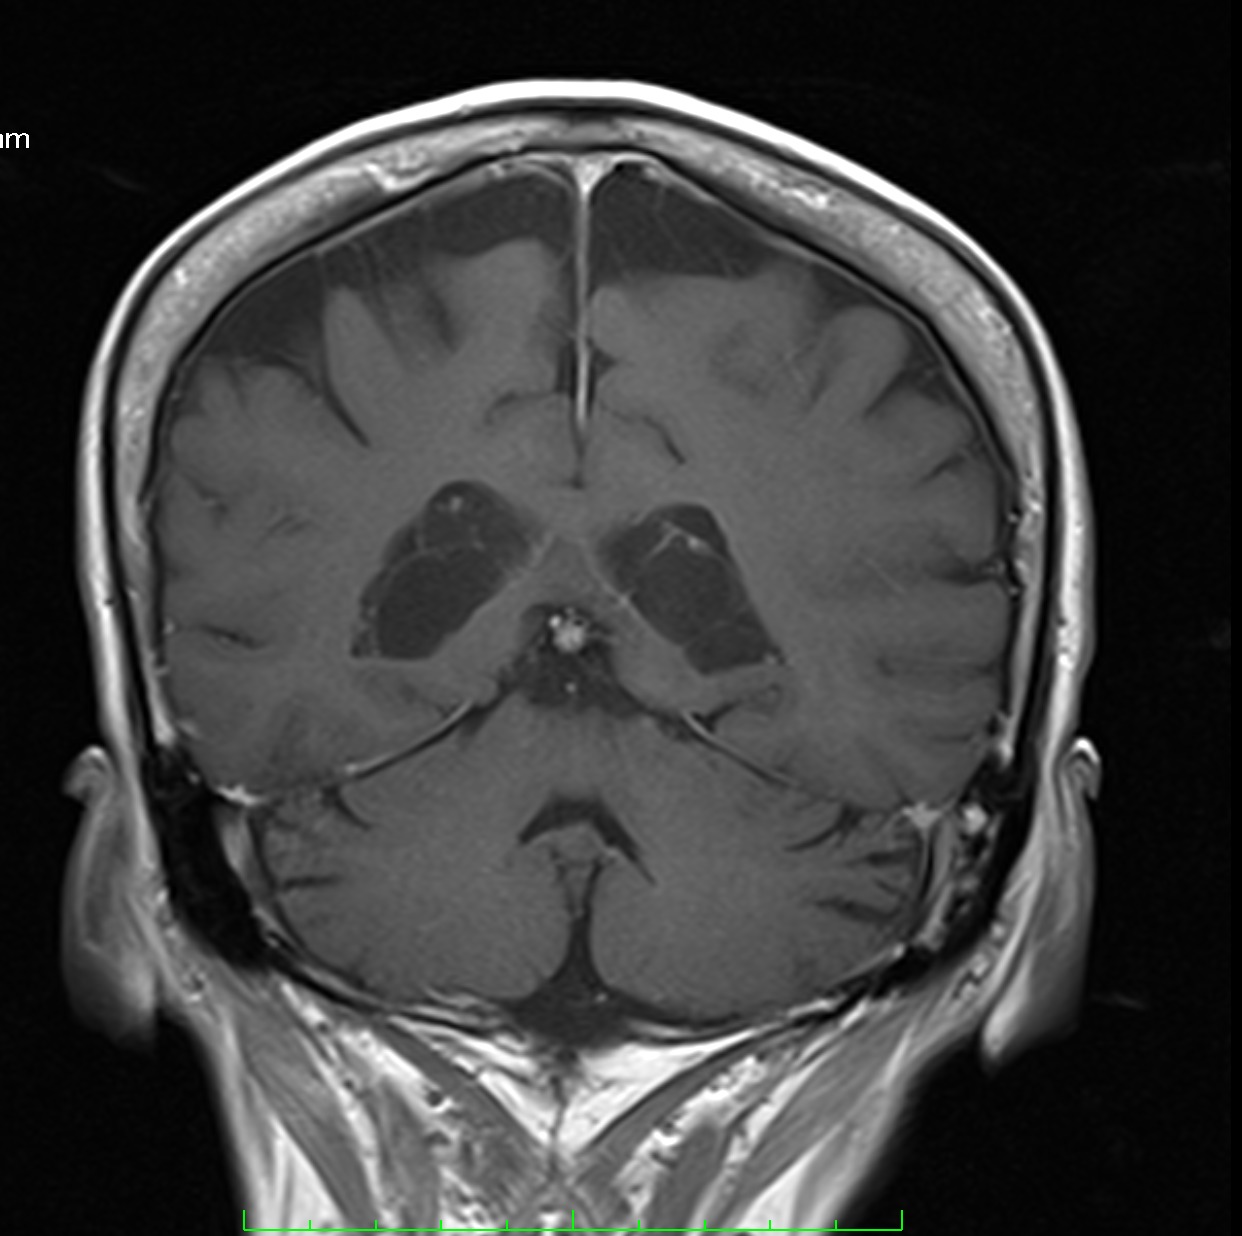

✔ Lesiones intraventriculares

✔Bilaterales

✔65% restringen en la secuencia de difusión

✔ Realce variable posterior a la administración de medio de contraste

✔ No hay edema del parenquima adyacente

NO DEBEN CONFUNDIRSE CON LESIONES TUMORALES INTRAVENTRICULARES!!!!